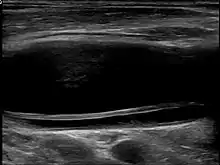

Carotid artery dissection

Carotid artery dissection is a separation of the layers of the artery wall supplying oxygen-bearing blood to the head and brain and is the most common cause of stroke in young adults.[1] (In vascular medicine, dissection is a blister-like de-lamination between the outer and inner walls of a blood vessel, generally originating with a partial leak in the inner lining.)[2]